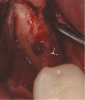

In a case presented in Figure 9 through Figure 11, the synthetic barrier was inserted at the time of removal of a tooth with significant bone loss on the palatal aspect (Figure 9). The rigidity of the material not only enabled containment of the bone replacement graft material, but also the initial formation of the site in the desired alveolar ridge shape (Figure 10). Six weeks later, there was no evidence of inflammation and the area was healing quite well (Figure 11). Not only was the alveolar ridge back to its ideal shape at the crest, but there was also a widened zone of keratinized tissue where primary closure was not attempted over the barrier.

Fig 9. A semi-rigid synthetic barrier was inserted in a subperiosteal manner where a significant loss of palatal bone and thin buccal plate existed.

Figure 9

Fig 10. The deficient socket was grafted and the barrier trimmed and positioned over the bone replacement graft material, enabling ideal formation of the final ridge shape.

Figure 10